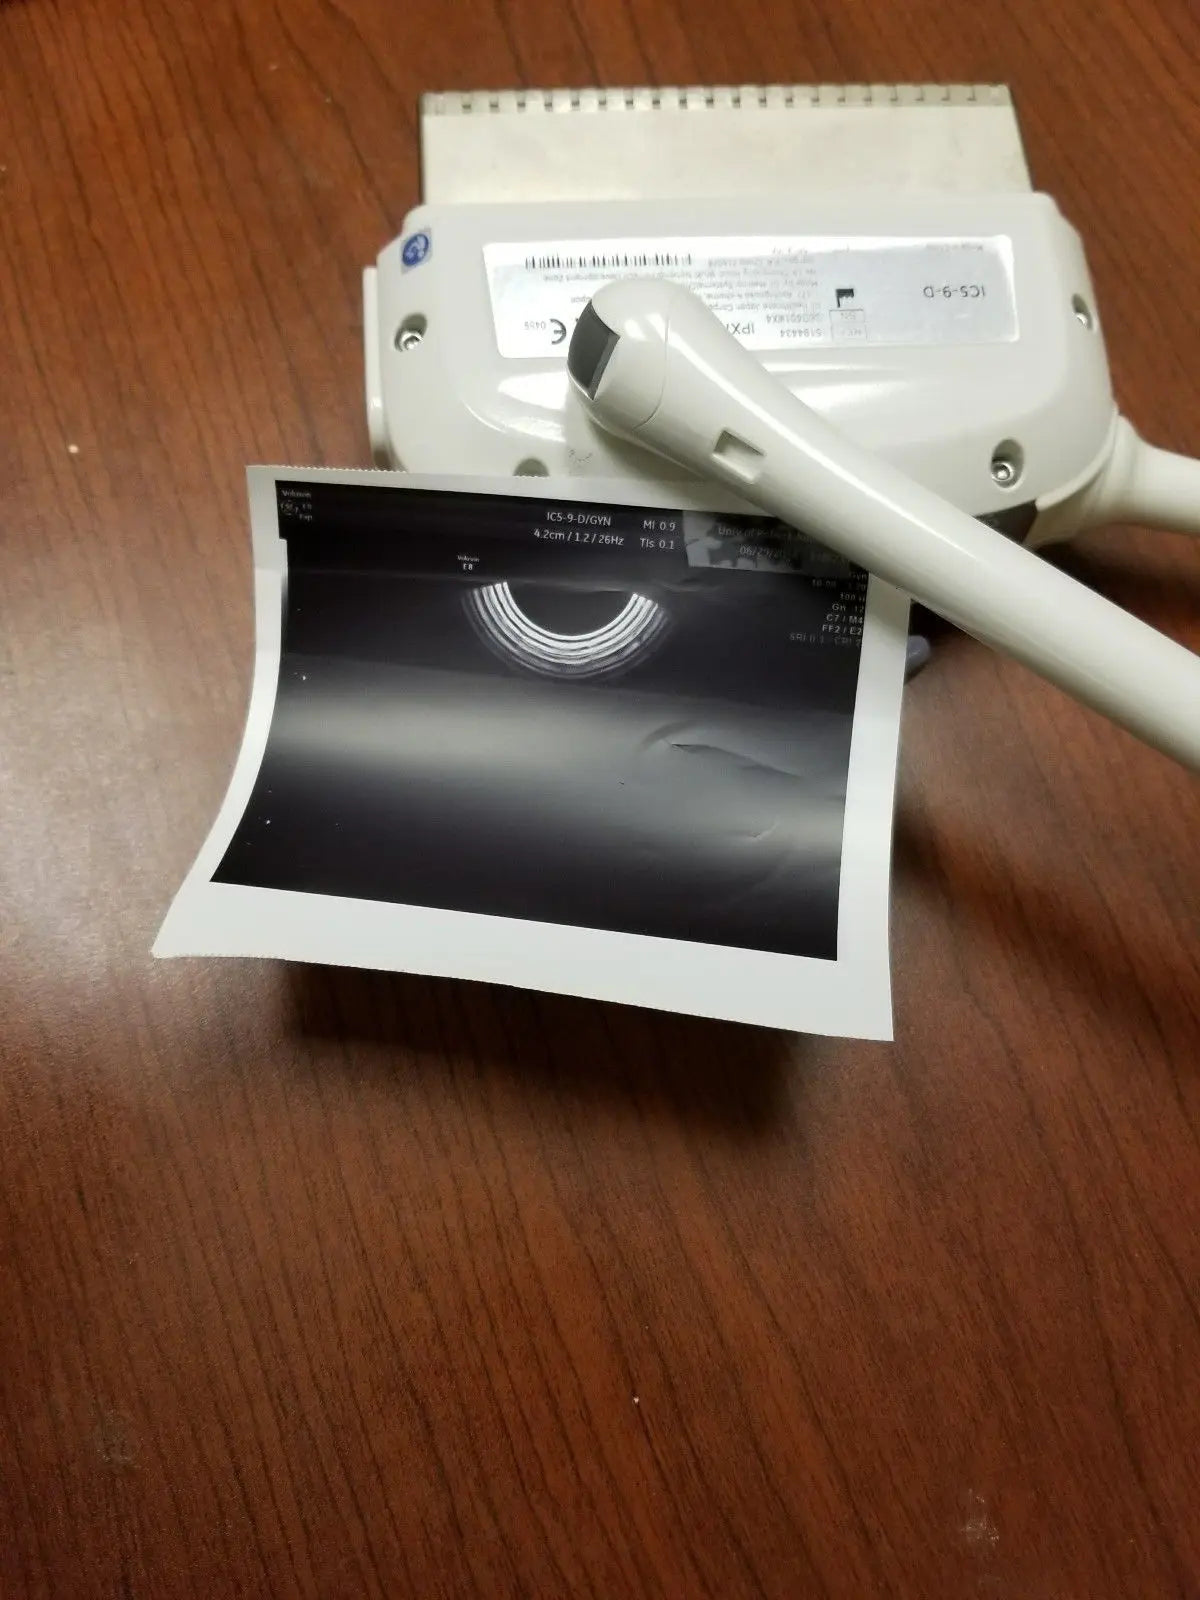

2017 GE IC9 -RS probe for GE Ultrasound

Sale price$ 8,395.14